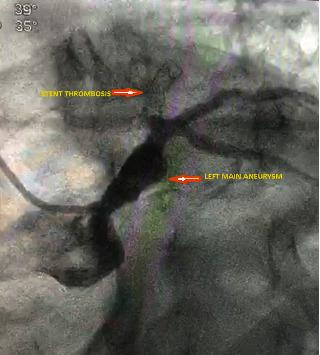

Coronary artery aneurysm (CAA) is a rare cardiac anomaly with a reported incidence of 0.3-4.9% of patients who undergo coronary angiography. The term is used when the coronary artery diameter exceeds more than 50% or 1.5 times the reference diameter. It can be congenital or acquired. The commonest acquired cause in an adult is atherosclerosis and in a child is Kawasaki's disease. The commonest culprit vessel is the Right Coronary Artery (RCA), followed by Left Circumflex (LCx) and Left Anterior Descending (LAD). Left main coronary aneurysms are extremely rare in clinical practice. Coronary angiography is the gold standard procedure, both for diagnosis and treatment. We report a 49-year-old male who presented with anterior wall ST-Elevation Myocardial Infarction (STEMI). The initial angiography showed LAD stent thrombosis, but when the second angiography was done, there was spontaneous recanalization of the LAD. Coronary angiography was performed at our hospital, which revealed a long left main coronary artery aneurysm measuring 9.8 mm-maximum diameter. This was treated with a size 5 × 24 mm Begraft coronary stent.

冠状动脉瘤(CAA)是一种罕见的心脏异常,在接受冠状动脉造影的患者中报告的发生率为0.3%-4.9%。当冠状动脉直径超过参考直径的50%以上或1.5倍时使用该术语。它可以是先天性的或后天获得的。成人中最常见的后天病因是动脉粥样硬化,儿童中是川崎病。最常见的受累血管是右冠状动脉(RCA),其次是左旋支(LCx)和左前降支(LAD)。左主干冠状动脉瘤在临床实践中极为罕见。冠状动脉造影是诊断和治疗的金标准程序。我们报告一名49岁男性,表现为前壁ST段抬高型心肌梗死(STEMI)。初次血管造影显示LAD支架血栓形成,但在进行第二次血管造影时,LAD出现自发再通。在我们医院进行了冠状动脉造影,显示一个最大直径为9.8毫米的长左主干冠状动脉瘤。使用5×24毫米的Begraft冠状动脉支架对其进行了治疗。